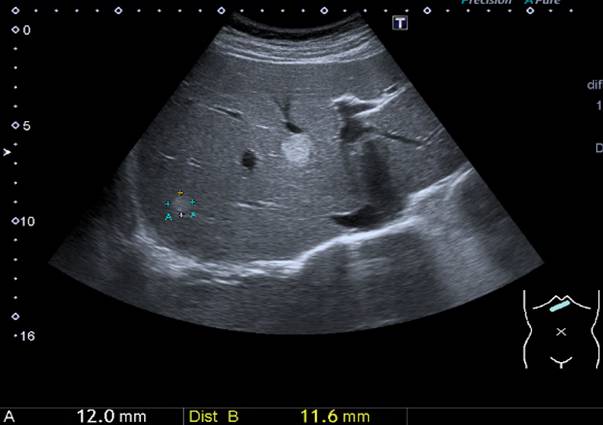

Figura X-5

Figure X-5